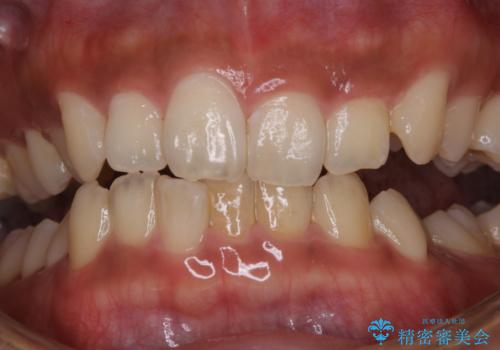

タバコによる着色をPMTCできれいな白い歯に

PMTCでは、歯の表面の凸凹にミネラルを補給して、ツルツルの表面に仕上げます。定期的にPMTCを行うことにより、歯質の強化になり着色がつきにくい状態になります。

普段の飲食物・歯磨き・生活習慣・喫煙の有無などにより着色の付き具合には個人差があります。どれくらいの頻度で行うことがベストかは、その都度担当の歯科衛生士とご相談します。